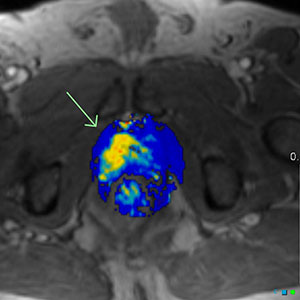

Standardní diagnostický postup u karcinomu prostaty v současné době zahrnuje vyšetření bioptických vzorků, které jsou z prostaty odebrány při tzv. transrektální biopsii prostaty naváděné ultrazvukem (zkratka TRUS pochází z anglického transrectal ultrasound-guided prostate biopsy). To znamená odebrání 10–12 vzorků z prostaty pomocí sondy vybavené speciální jehlou. Po aplikaci lokálního anestetika je do pacientova konečníku zavedena sonda, kterou následně lékař provádí samotnou biopsii. Jedná se o poměrně nepříjemnou a drahou proceduru, která s sebou navíc nese nepatrné riziko infekce; kromě samotné biopsie je účelem TRUS odhadnout místo, kde se nachází potenciální nádor, jenže v praxi zůstávají často některé nádory neodhaleny [3]. Studie PRECISION se zabývala otázkou, zda by se při vyšetření pomocí MRI mohli někteří pacienti vyhnout zbytečné biopsii, a zda v případech, kde je biopsie nezbytná, jsou získané diagnostické informace přínosnější než při TRUS.

Výzkumníci z 23 center náhodně rozdělili celkem 500 mužů do dvou skupin: jedna skupina byla vyšetřována standardní procedurou TRUS, kdy bylo odebráno vždy 10–12 vzorků, zatímco druhá skupina podstoupila vyšetření pomocí MRI, po kterém následovala cílená biopsie pouze v případech, kdy byla při magnetické rezonanci zjištěna nějaká abnormalita. Primárním cílem studie bylo zjistit, u jakého podílu mužů bude diagnostikován klinicky významný karcinom prostaty (definovaný jako Gleasonovo skóre ≥3+4), což je potenciálně fatální typ nádoru a jeho diagnostika má tedy zásadní význam. Jedním ze sekundárních cílů studie bylo zjistit, u jakého podílu mužů bude diagnostikován klinicky nevýznamný karcinom prostaty (definovaný jako Gleasonovo skóre 3+3), jehož léčbě je lepší se vyhnout, neboť pro pacienta neznamená prakticky žádný přínos.